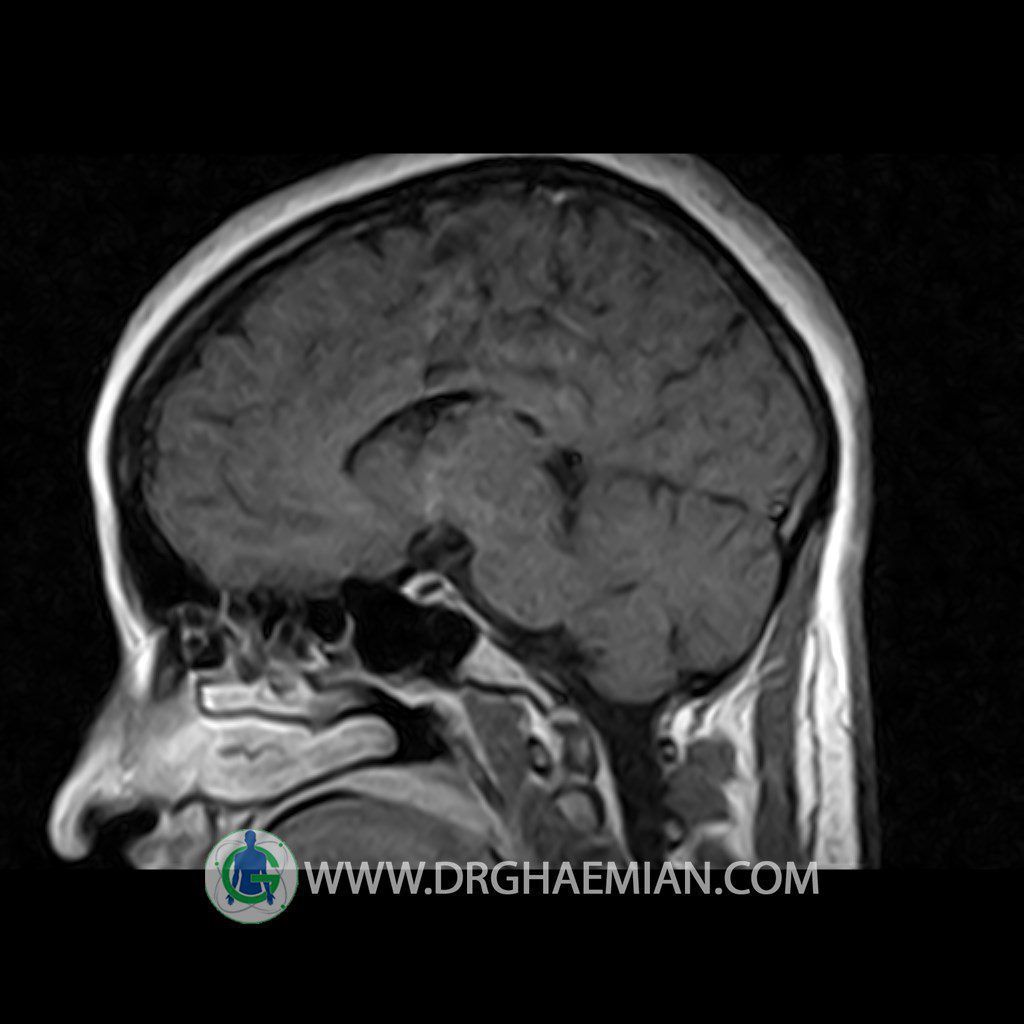

ام آر آی هیپوفیز یک روش تصویر برداری است که از غده هیپوفیز (غده ایی کوچک در مغز که هرومون ها و دیگر غدد بدن را کنترل می کند) و ناحیه های پیرامونش در مغز تصاویری ایجاد می کند. در این کیس سلای نسبتا خالی در ناحیه هیپوفیز بیمار مشاهده می شود.

Technique: Axial , coronal T1 , Axial , coronal , sagittal T2 , Axial, coronal T1 post Gd & 64 dynamic thin coronal slices.

The pituitary tissue shows normal , position, shape , size and homogeneous signal intensity both before and after contrast administration .

Anterior and posterior pituitary gland were normal .

– Extension of suprasella cistern to sella with thin pituitary gland in floor of sella ( partial empty sella )

is seen